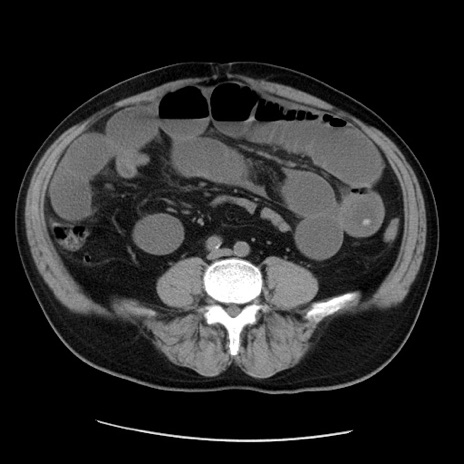

症例20(横断像)

【症例】 60歳代男性

【主訴】 腹部膨満、嘔吐

【現病歴】5日前頃より倦怠感を認め食事量減少し4日前の朝嘔吐、食事摂取困難となった。 3日前近医受診し点滴施行され整腸剤などを処方された。 当日他院を受診し、腹部膨満著明、炎症反応の上昇(CRP10.8、WBC11200)あり、紹介受診となる。

【身体所見】 意識JCS1 受け答えがはっきりしないBP 111/57mHg、 P 67bpm、、BT35.2°C、SpO2 97%(RA)、 腹部:膨隆、打診で鼓音あり、全体的に圧痛有り、腸蠕動音(-)、反跳痛ははっきりせず。

【データ】WBC 11400、CRP 14.20